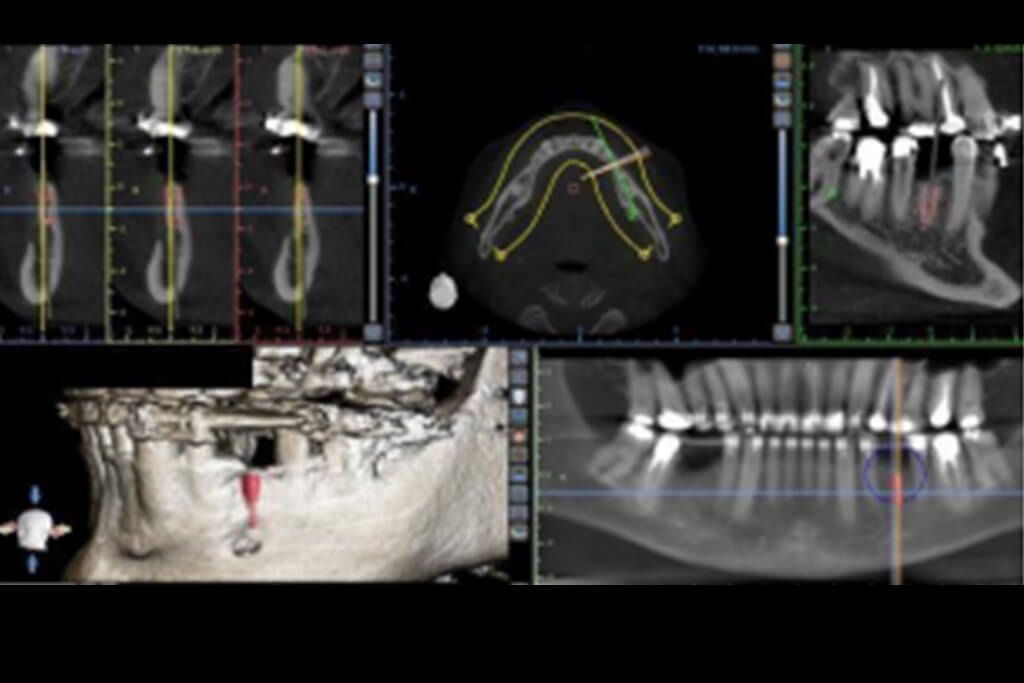

Após uma anamnese detalhada, o paciente foi submetido a exames clínicos e de imagem (tomografia computadorizada), que confirmaram a necessidade de um aumento ósseo horizontal para criar a base óssea necessária para a instalação dos implantes. A tomografia revelou a redução da largura óssea na região posterior da mandíbula, em torno do local onde o implante seria instalado.

A decisão foi tomada em conjunto com o paciente para realizar o aumento ósseo utilizando a técnica de Khoury. Para o planejamento da cirurgia, foi realizada uma análise digital da situação clínica, e o planejamento tridimensional foi feito com o auxílio do CAD/CAM, permitindo a visualização precisa da área a ser enxertada e a criação de uma estratégia de incisão, remoção do enxerto ósseo e posicionamento do implante. (Imagem 01a e imagem 01b)

Esse espaço foi preenchido com partículas ósseas autógenas, provenientes do ramo mandibular em conjunto com o enxerto xenógeno de origem bovina, o que ajudou a garantir a estabilidade das duas lâminas do ramo mandibular e favoreceu a regeneração óssea. Esse enxerto ósseo em bloco foi cuidadosamente preparado e posicionado na área da perda óssea na região posterior da mandíbula, logo após foi realizado a síntese, fase final da etapa cirúrgica e assim foi realizado a tomografia computadorizada para a verificação da posição do implante dentário. (Imagem 08A, Imagem 08B, 08C e 08D)